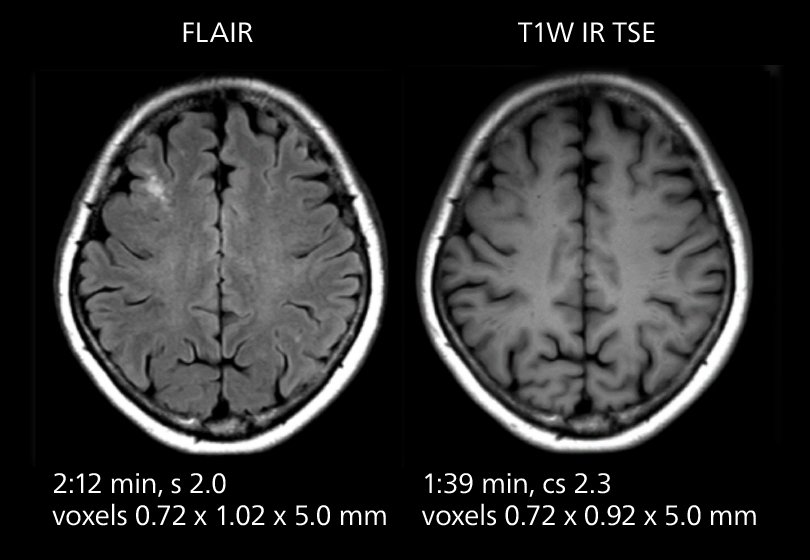

Brain MRI

These images of an old cerebral infarction demonstrate the speed and image quality after upgrading to Elition X.

Brain MRI

These images of an old cerebral infarction demonstrate the speed and image quality after upgrading to Elition X.